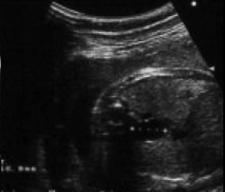

Image echographique prenatale

duplication kystique de oesophage ( coupe

transverse ) |